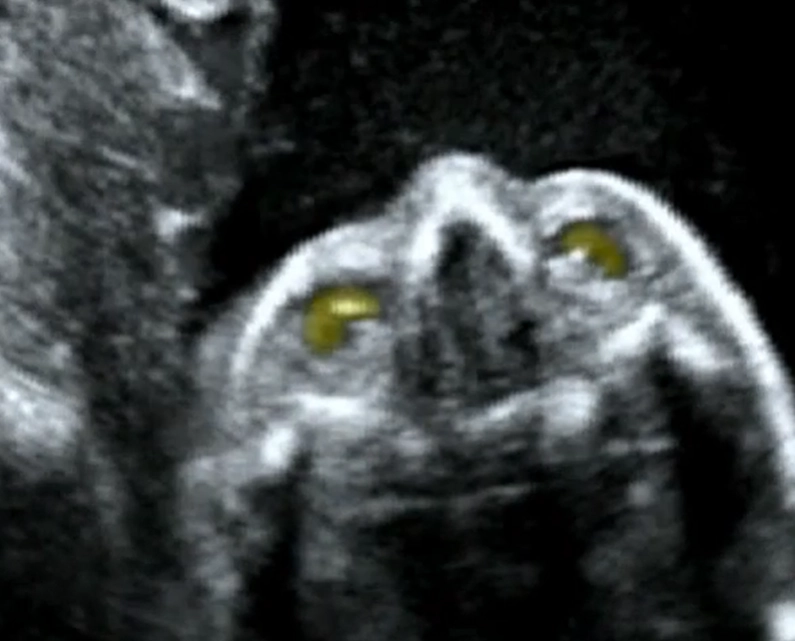

Đục thủy tinh thể thai nhi (Cataracts)